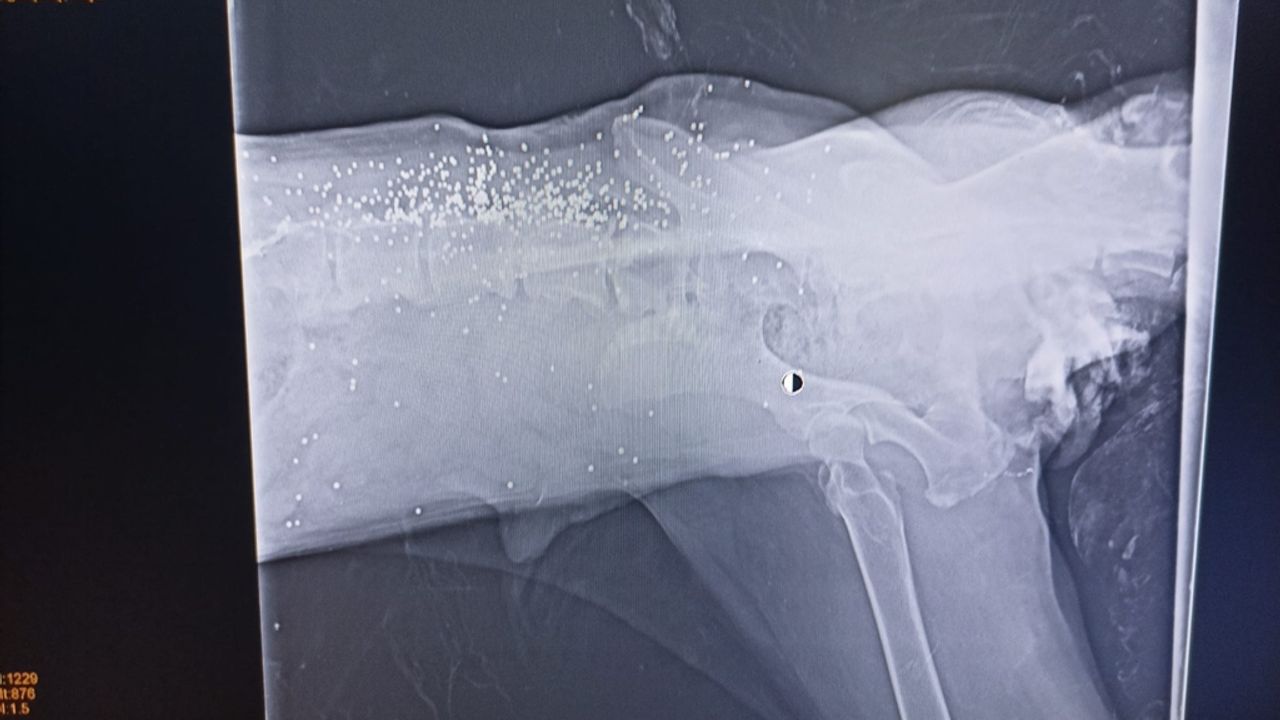

Bolu Belediyesi Veteriner İşleri Müdürlüğü'nde tedaviye alınan köpeğin, araç ezmesi nedeniyle arka bacaklarının kırıldığı belirlendi. Veterinerlikte çekilen röntgende köpeğin daha önce av tüfeğiyle vurulduğu tespit edildi. Köpeğin kalça ve bel bölgesinde saçmalar olduğu görüldü. Daha önce aksayarak yürüyen köpeğin, yürüme yetisini tamamen kaybettiği öğrenildi. (DHA)